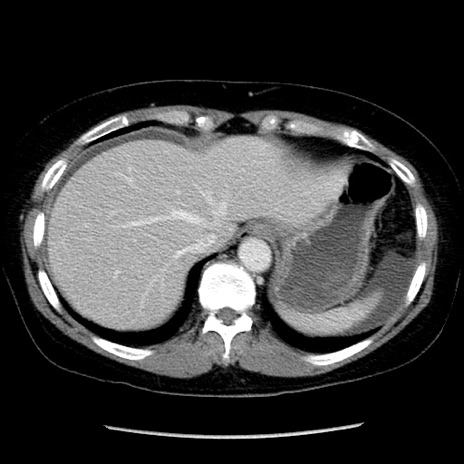

症例6(横断像)

【症例】50歳代女性

【主訴】下腹部痛

【現病歴】本日朝より下痢2回あり。 昼食を食べた後、嘔吐3回、下腹部痛認め、症状軽快せず、当院救急搬送。

最終食事:本日昼(生ものなし)。 昨日の夜、刺身を食ぺたとのこと。周囲に同様の症状の者なし。普段、排便は毎日あるとのこと。

【既往歴】卵巣癌術後(8年前に当院で卵巣摘出)

【身体所見】 意識清明、腹部:平坦、腸蠕動音→、やや硬、下腹部自発痛・圧痛あり、反跳痛あり、筋性防御なし。

【データ】WBC 16000、CRP 0.01